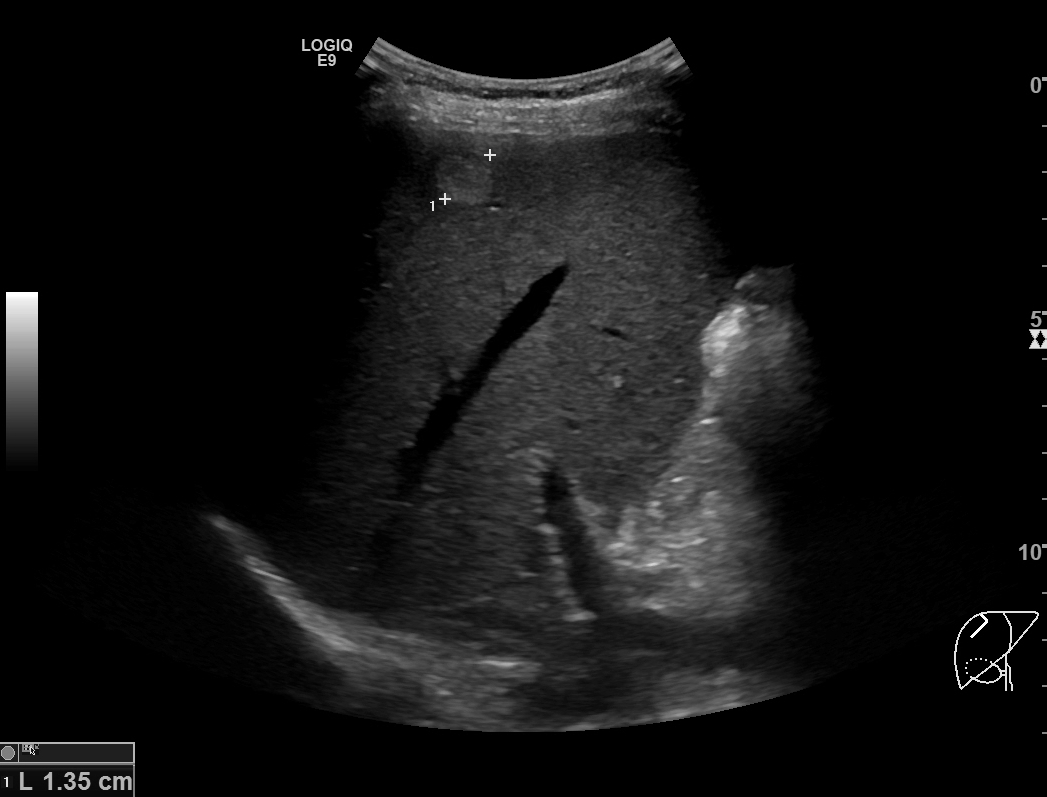

2개월 후 담낭염의 호전여부를 확인하기 위해 간초음파를 시행했습니다. 담낭벽비후는 깨끗하게 호전되었는데, 간우엽에 고에코음영의 종괴가 발견되었습니다. 이전 복부CT영상을 다시 확인해도 전혀 보이지 않는 종괴였으며, 크기가 1.7센티미터로 크기가 작아서 확인이 안될 상황은 전혀 아니었습니다.

종괴는 균일한 고에코음영을 보였지만, 후방에코강조(posterior acoustic enhancement)가 보이지 않았고 모양도 각이 지고 약간 불규칙한 형태를 보였기 때문에 간혈관종의 가능성은 떨어졌기에 추가적인 확인을 위해 간의 다이나믹 조영증강 영상을 추가로 시행했습니다.